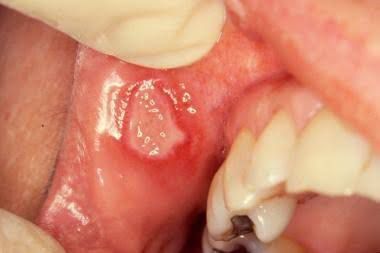

An aphthous ulcer is typically a solitary round sore or ulcer inside the mouth on an area where the mucosa is not tightly bound to the underlying bone, such as on the inside of the lips and cheeks or underneath the tongue Major aphthous ulcer(pictured) is a type of Aphthous ulcer which is large (often more than 10 mm) and takes weeks or months to heals with scarring. The main goal of treatment is to decrease the pain and discomfort and promote healing. Credits: https://dermnetnz.org/topics/aphthous-ulcer/ https://images.app.goo.gl/nc9VgZCyDxtzb2d4A